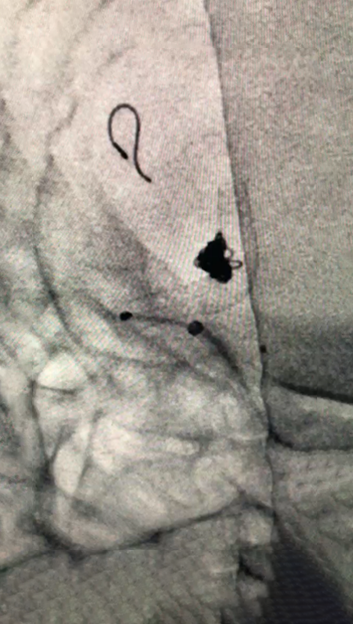

CT造影

1.1)

Echelon微导管塑形,瘤颈口到位

1.2)

Navien + Phenom助力上高到颈内动脉末端